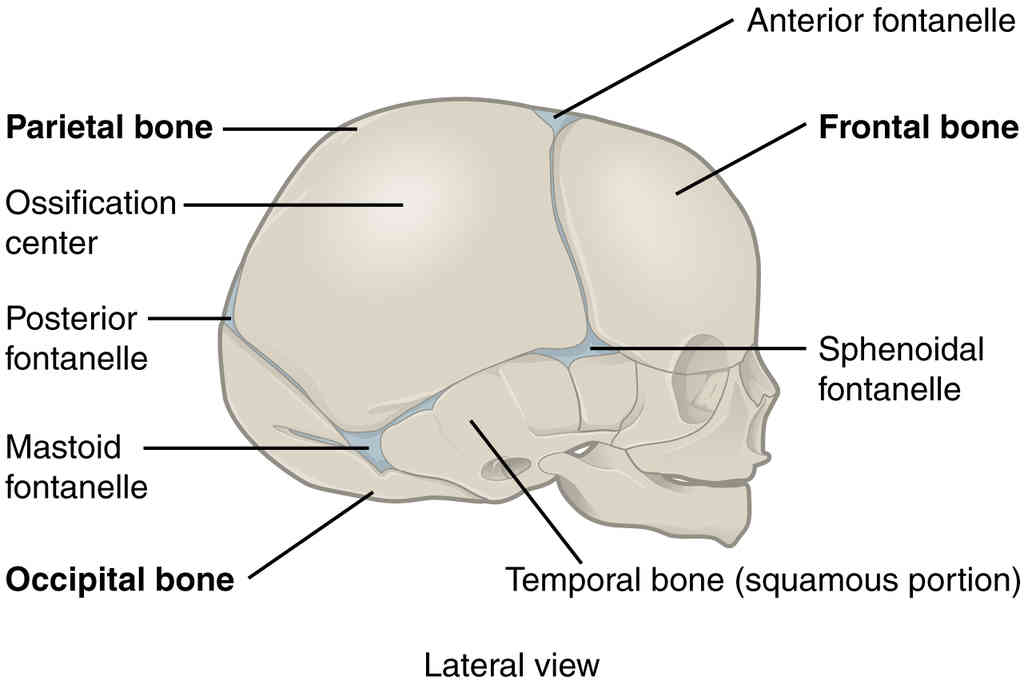

This page is under construction. For now, it is just a resource of the images found in the OpenStax Anatomy and Physiology Handbook. It wil slowly change into a revision tool. Each slide has a number. Use this to refer to the slide. When completed, it will have an unlabelled section, with labelled slides in parallel. On the unlabelled slides, write your answer and use the labelled slide to assess yourself. Keep track by also noting the number on each slide. Improvement at each attempt is important, more so than full marks on a first attempt.